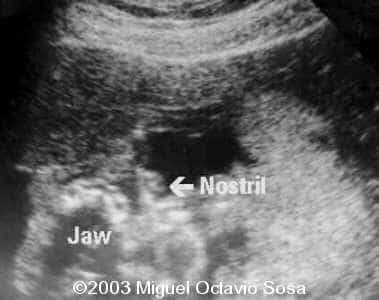

19-year-old primigravida. During third week of pregnancy, she is vaccinated with anti-measles vaccine, without knowing about the pregnancy. There are no important details before the pregnancy. These are images of the face of the fetus. Pay specific attention to the midface.

19-year-old primigravida. During third week of pregnancy, she is vaccinated with anti-measles vaccine, without knowing about the pregnancy. There are no important details before the pregnancy. At 22nd week, an ultrasound is performed demonstrating a single nasal channel on the left side and absence of right nostril.